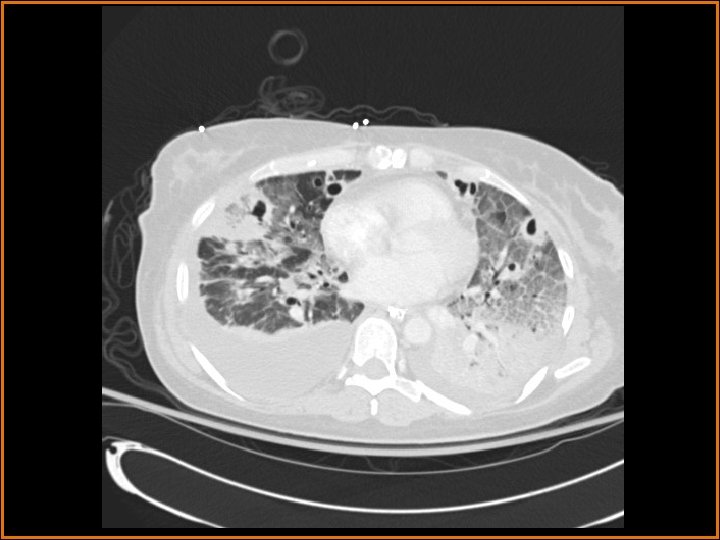

Findings and Differentials CT Findings: Multiple bilateral peripheral nodular opacities are seen, many of which are fed by arterial branches. Some of the nodules are cavitary. Diffuse bilateral ground glass opacities are seen with air bronchograms. The large lucency projecting over the right hemidiaphragm on the plain film corresponds to a pleural air collection that is directly contiguous with one of the cavities. Differential Diagnosis: • Multiple cavitary metastases • Septic Emboli

Discussion (Continued) In this patient, the large right anteroinferior pleural air collection is contiguous with one of the cavities (as seen on the second CT image) and represents a bronchopleural fistula. Etiologies of bronchopleural fistulas include necrotizing infection, active TB, irradiation, tumor in a bronchial margin, etc. If the bronchopleural fistula is large, a persistent pneumothorax with or without contralateral mediastinal shift may be present. In this case, a septic embolus had eroded into the pleural space, creating the lucent collection projecting over the right hemithorax on the plain films. Finally, the ground glass opacities represented pneumonia in this patient.